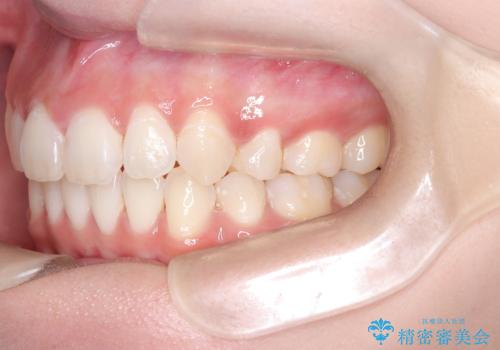

【インビザライン】シザーズバイト、抜歯矯正

- オープンバイトを主訴に来院された患者様です。

抜歯を行うことで、インビザラインを用いて前歯を下げることができ、同時にオープンバイトを改善することができました。

今回はインビザラインのみで治療を終了することができました。